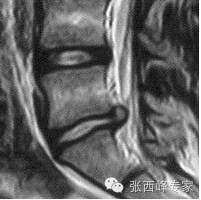

核磁矢状位腰5骶1椎间盘突出